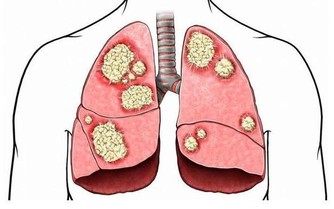

而很多人不知道的是,腳上有很多經絡通向肝臟,通過觀察腳上的變化就能判斷肝臟的健康狀況。

腳上出現這4個信號,說明你的肝越來越差!

正常健康腳掌顏色應是白裡透紅,如果腳掌發白,無血色,可能是血液垃圾過多,致使血管淤堵,供給腳掌的血液不夠,腳掌自然呈現出發白的症狀,出現這種情況且伴有頭暈、眼花、無力等症狀時,應留意肝臟健康。

中醫學認為,正常腳底顏色略紅。排除一些角質層較厚的人會出現腳底發黃之外,還可能與肝臟有關係,當肝細胞破壞,使得血中的膽紅素不能正常的排除,逆流至血液中,呈現出腳底發黃。

很多人認為,腳底乾燥是因為腳部皮膚疾病而導致的,殊不知腳底肌膚與身體內分泌有關,當肝細胞受損時,可能影響身體內分泌正常,進而導致皮膚暗黃、腳底變得乾燥,常出現脫皮、乾裂情況,這些情況應留意是否是肝臟受損。

中醫認為,肝主藏血,肝臟每天會分解血液中的毒素或代謝產物,當肝臟受損時,其解毒能力也會有所下降,血液健康也可能受到一定影響。腳距離心臟較遠,如果腳掌紋路增多且變得明顯,要注意腳下保暖和保養肝髒了。